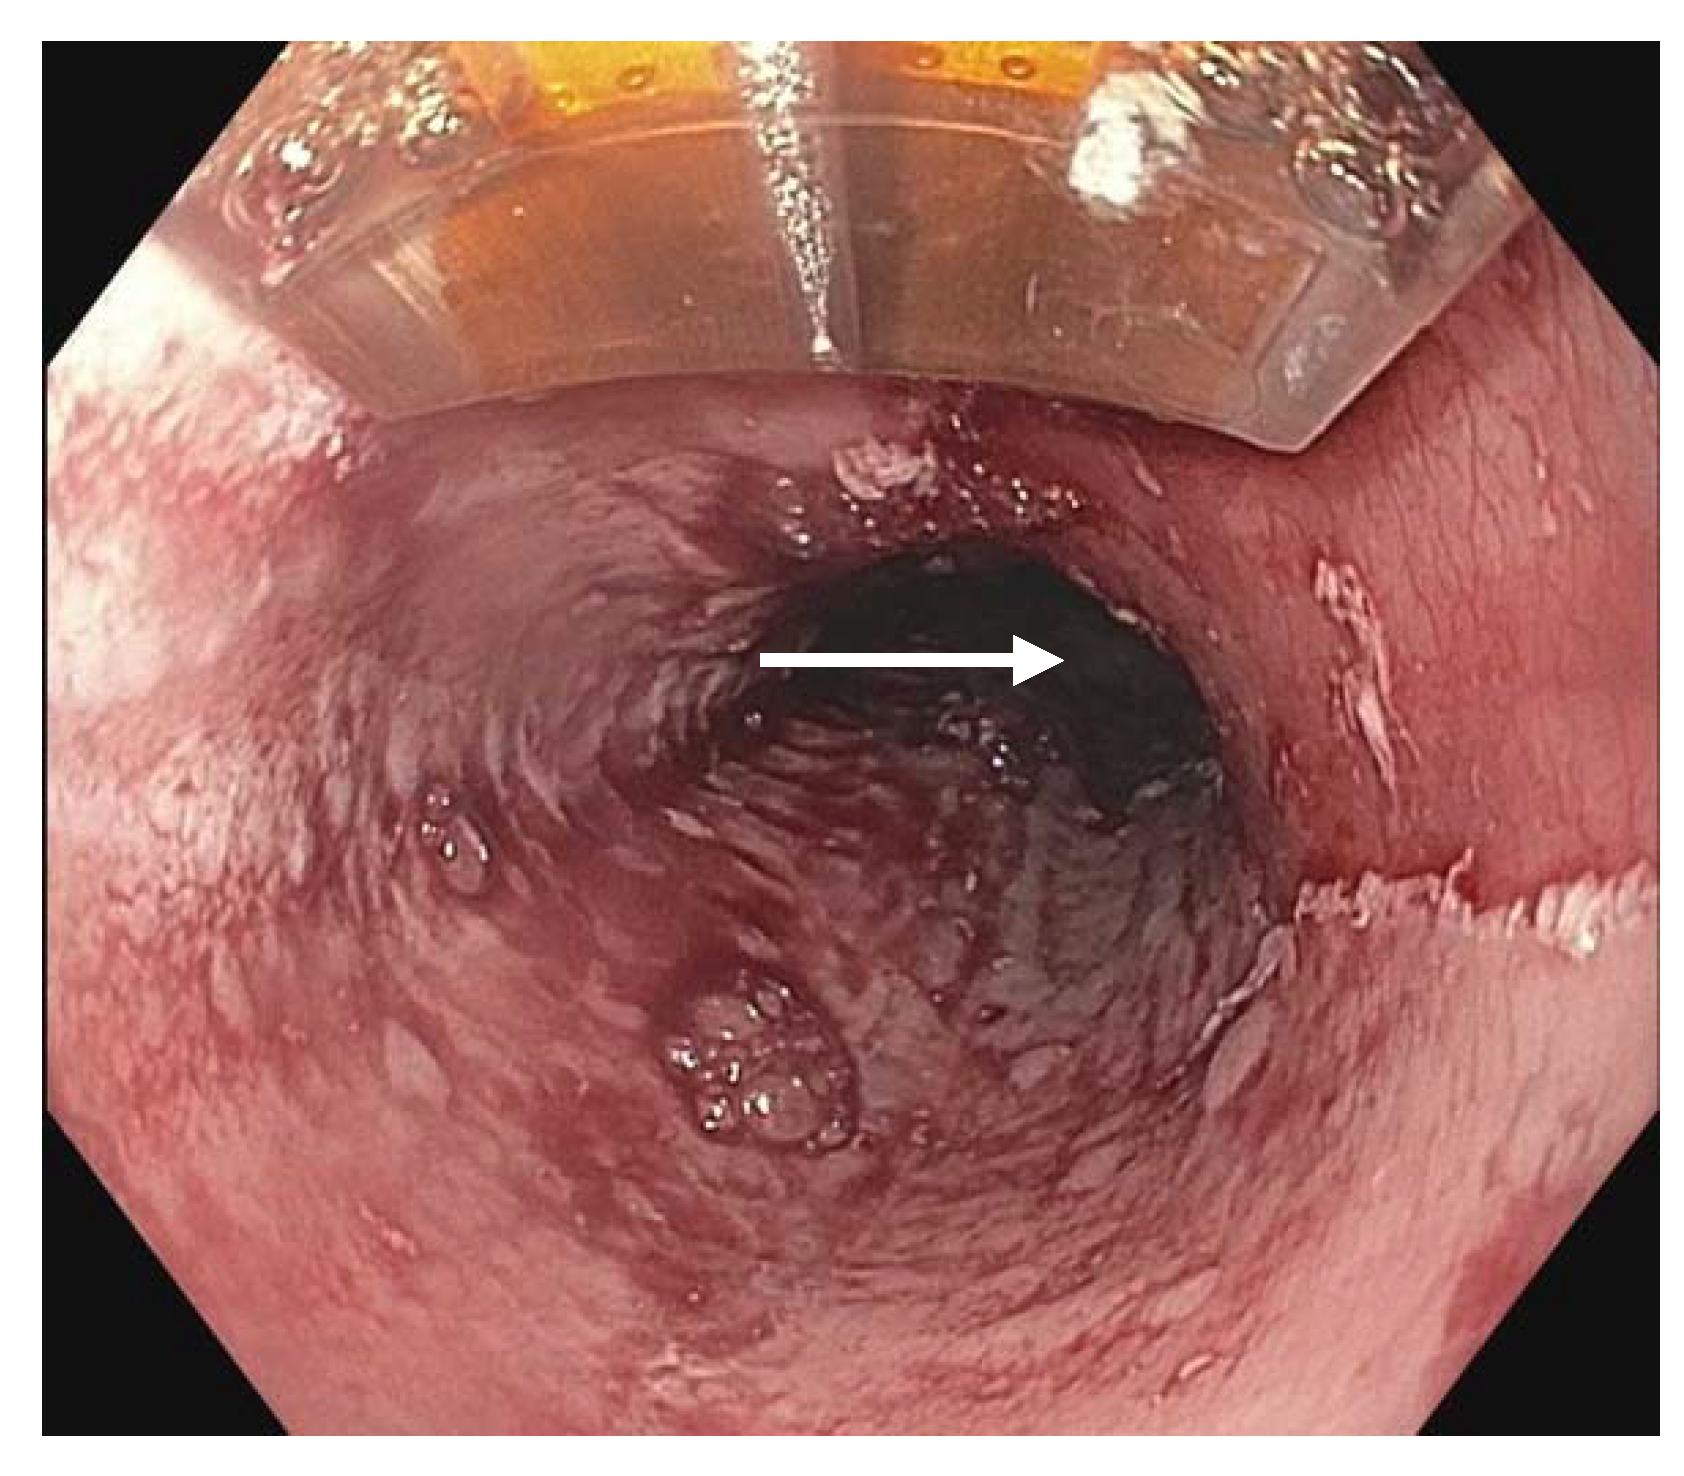

Radiofrequency ablation (RFA) (Figure 3) can be employed to eradicate circumferential areas of dysplastic BE. It is often used in conjunction with EMR for complete diagnosis and treatment; nodular BE requiring EMR for appropriate resection and non-nodular BE benefiting from targeted or focal ablation. When required for complete eradication following initial EMR or EMR with RFA, serial RFA is typically performed every 3 months [81,82].

Figure 3.

Radiofrequency ablation being applied using a probe toa dysplastic mucosal area (white arrow).

RFA has been shown to be highly effective in completely eradicating intestinal metaplasia and all grades of dysplasia and neoplasia, and on average required 3–4 treatment sessions for eradication [81]. Pooled CE-IM rates of 78% and rate of complete eradication of dysplasia (CE-D) of 91% [82]. It was found that pre-treatment histology was a non-significant determining factor in efficacy, with LGD more likely to demonstrate CE-IM and CE-D than HGD and/or intramucosal cancer [82]. Characteristics associated with incomplete eradication included BE segment length, incomplete healing between serial RFA therapy, and requirement of more treatment sessions [81]. RFA treatment failure can be difficult to define by threshold number of treatment sessions given that cases have been successfully eradicated following more than four or five sessions. RFA is widely accepted as first-line therapy given efficacy and safety; however, adverse effects can include, most commonly, strictures, bleeding, and pain.